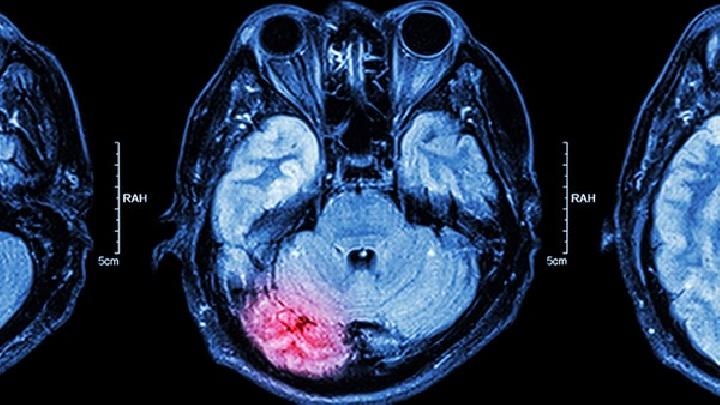

颅骨损伤作为一种常见的外科损伤,在任何医院都非常重视,因为它可能导致许多疾病、瘫痪甚至死亡。鉴于颅骨损伤的严重后果,患者家属及时安排患者治疗是重点,医院的科学、专业和持续护理是首要任务。

观察患者的意识、瞳孔、生命体征和身体活动,警惕颅内出血、继发性脑水肿和癫痫。